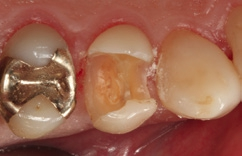

Bei dem 57-jährigen Patienten imponierte in der Routine-Bissflügelaufnahme eine Sekundärkaries an dem mit einem Gold-inlay versorgten Zahn 14 (Abb. 1). Der vitale und symptomfreie Zahn zeigte lediglich radiologisch (Abb. 2) einen Randdefekt distal sowie den Verdacht auf Karies unter dem Befestigungs- bzw. Unterfüllungszement. Nach Entfernung des Goldinlays ergab sich der Verdacht auf eine Pulpaeröffnung (Abb. 3). Klinisch war keine Blutung feststellbar, was allerdings durch die Lokalanästhesie kaschiert sein konnte. Aufgrund der Symptomlosigkeit des Zahnes und fehlender Anzeichen einer Pulpitis (fehlende Blutung) sowie einer Nekrose (erhaltene Vitalität) fiel die Entscheidung zugunsten einer Vitalerhaltung unter Beibehaltung eines engmaschigen Recalls mit Vitalitätsproben. Die Überkappung der Eröffnungsstellen erfolgte als Alternative zu Calciumhydroxid [8] mit einem Portlandzement enthaltenden Flowkomposit mit hohem pH-Wert [7,51] (TheraCal LC, Bisco, Abb. 4). Obwohl dieses Produkt hinsichtlich seiner Effektivität und Zelltoxizität nicht an ProRoot MTA (Dentsply Sirona) und Biodentine (Septodont) [42] herankommt [5,11], ist es hinsichtlich seiner Praktikabilität und der Möglichkeit des sofortigen, zügigen Weiterarbeitens konkurrenzlos. Ein vergleichbares Produkt gibt es z.B. bei Ultradent (Ultra- Blend Plus).

Die Weiterversorgung erfolgte nach adhäsiver Vorbehandlung mit einem approximal eingebrachten 4-mm-Inkrement SDR flow+ (Dentsply Sirona) in der Farbe A3, klassisch überschichtet mit ceram.x universal in der Farbe A3,5. Die Wahl auf ein Bulk-Flow-Komposit approximal fiel aufgrund der optimalen selbstnivellierenden Adhäsion zum Adhäsiv und somit zur Reduktion potenzieller Fehlerquellen in der Schichttechnik, die Wahl zugunsten des eingefärbten SDR flow+ in der Farbe A3 entgegen der transluzenten Universalfarbe U aufgrund der im Approximalraum dunkel erscheinenden Gold-Restauration am Nachbarzahn. Dies ergab in der Vergangenheit bei Verwendung von SDR flow+ U oft ein unschönes „grau-transluzent“ erscheinendes Bild der Kompositrestauration im Approximalraum. Ästhetisch störte dies meist nur bedingt, suggerierte aber immer die latente Möglichkeit einer Approximalkaries. Durch die Verwendung der Farbe A3 bei SDR flow+ war ein derartiges grau-transluzentes Erscheinungsbild nicht mehr gegeben; die Restauration erscheint homogener (Abb. 5). Die Abbildung 6 zeigt die Röntgenkontrollaufnahme nach einem Jahr, die Abbildung 7 die klinische Situation: Der Zahn ist weiterhin vital, symptomlos und beschwerdefrei. Direkte Kompositrestaurationen stellen heute gerade bei vorangegangenen Goldinlay-Kavitäten die suffizienteste Sekundärversorgung dar: Der vorhandene Federrand kann belassen werden und muss nicht in eine plane Stufe einer Keramikrestauration umpräpariert werden.